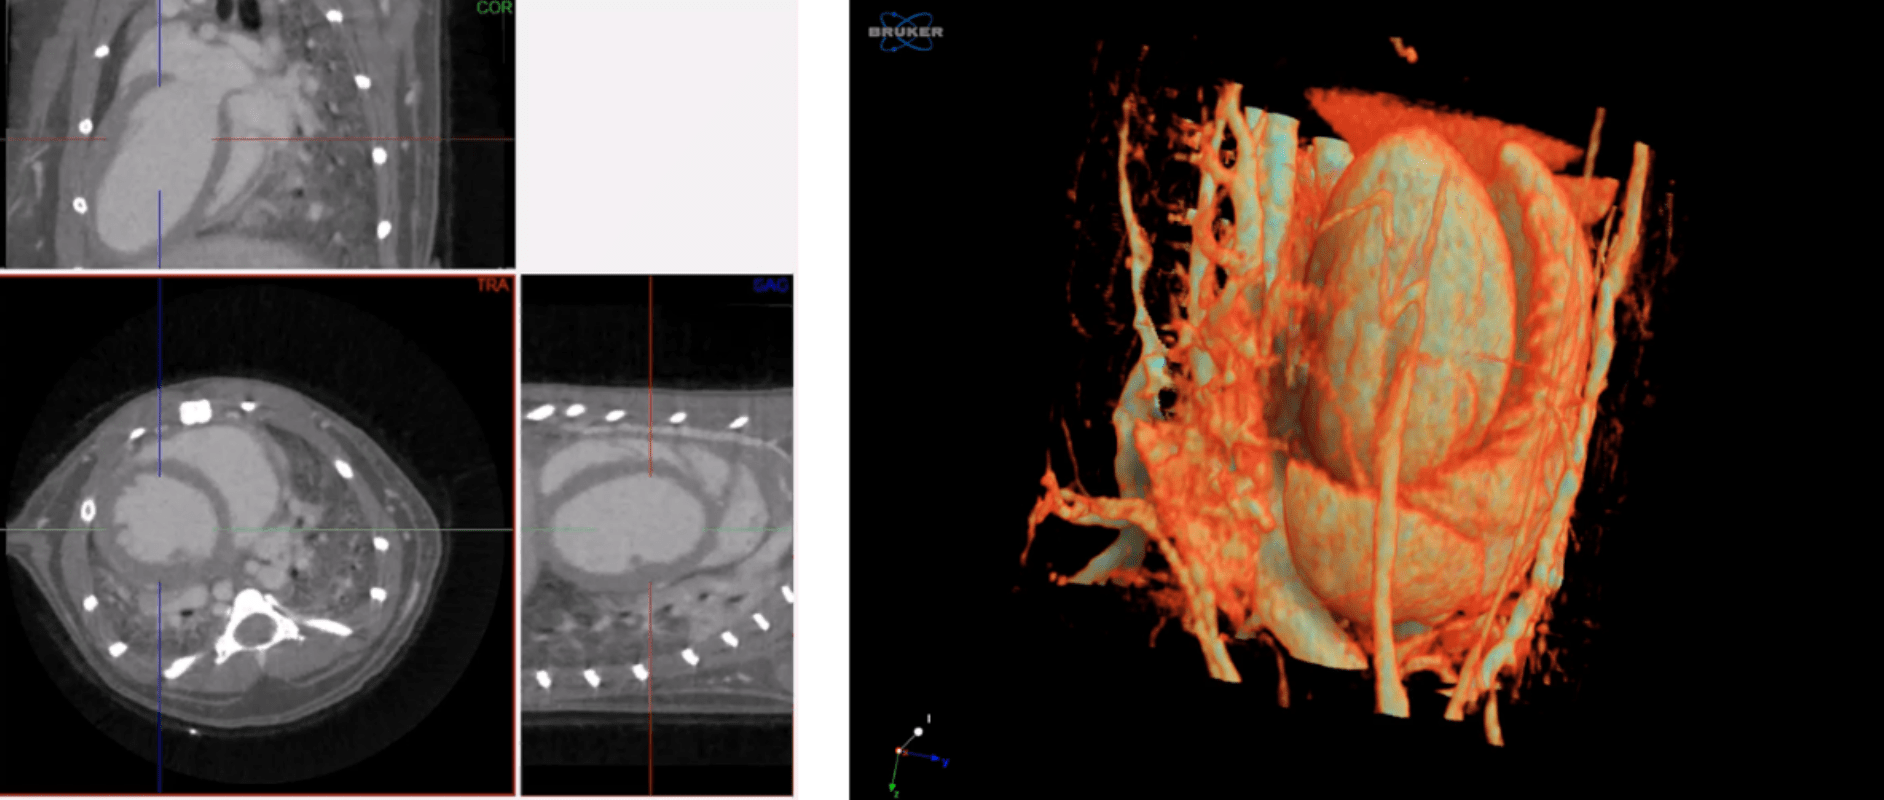

Cardiac gating

Time resolved imaging doesn’t have to be limited to the lung. By combining SkyScan’s unique LISTMODE acquisition function—collecting very fast images during the acquisition phase and then sorting post-data collection—with the use of perfused contrast agents in vivo, time resolved images of the heart can be acquired and volumetric analysis of blood flow at different stages can be calculated.